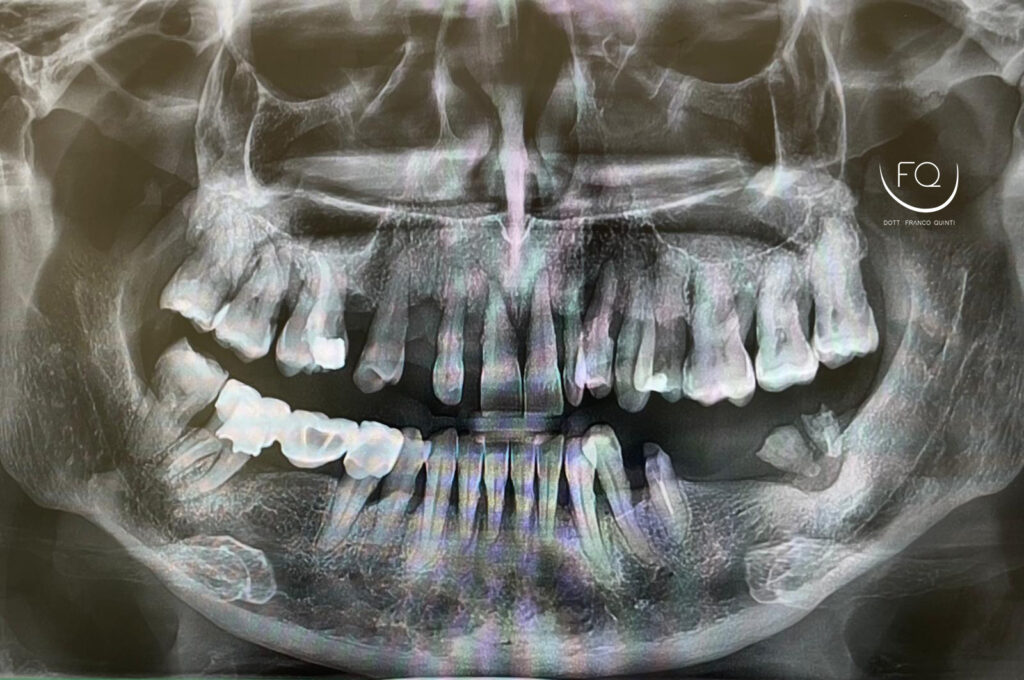

Oggi vi presento il caso di un paziente affetto da parodontite in fase terminale.